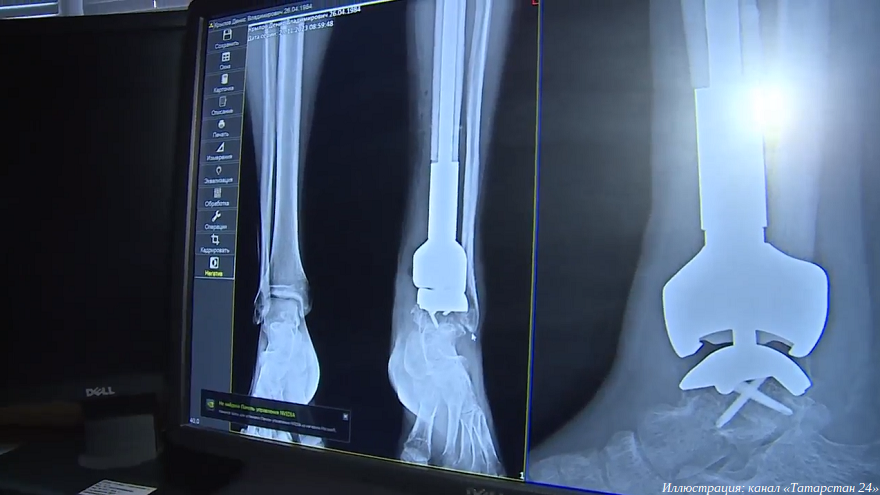

Врачи татарстанского республиканского онкологического диспансера установили 3D-печатный эндопротез

Жителю Казани пересадили титановый эндопротез, созданный с помощью 3D-принтера. Нога пациента была под угрозой ампутации из-за рака костей. Подобная операция в Татарстане проведена впервые.

Пораженную раком кость заменили титановым эндопротезом, изготовленном на 3D-принтере в Самаре за три недели, сообщает канал «Татарстан 24». Необходимость в поиске новых методов лечения опухолей костей стала актуальной после ухода зарубежных поставщиков эндопротезов с российского рынка. Операцию провела команда заведующего отделением опухолей костей, мягких тканей и кожи Республиканского клинического онкологического диспансера имени профессора М. З. Сигала Ильдара Сафина.